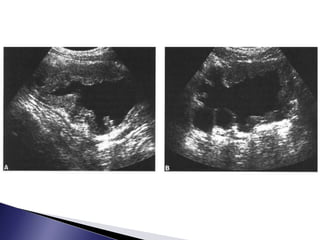

 Ecografía

 Descarta malformaciones

congénitas renales

 Evalúa tamaño renal y

morfología

 58% identifica litiasis

 Valora ecogenicidad el

parénquima y si existe o no

edema

 Distingue presencia minima de

liquido perirrenal subcapsular

por las disrrupciones del

fórnix

 Ecografía  Descartamalformaciones congénitas renales  Evalúa tamaño renal y morfología  58% identifica litiasis  Valora ecogenicidad el parénquima y si existe o no edema  Distingue presencia minima de liquido perirrenal subcapsular por las disrrupciones del fórnix